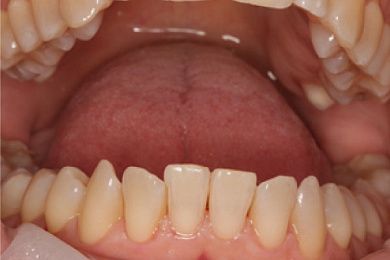

Результат лечения